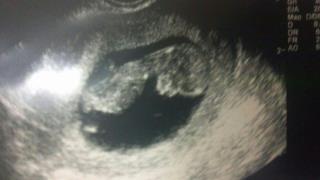

A friend asked me to post this u/s, taken at 10W5D. She's looking for guesses based on the skull theory since it's too early for a nub.

Sorry it's upside down.